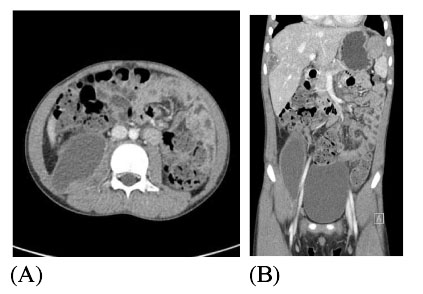

(A). A cross sectional view of the abdominal CT with contrast shows huge iliopsoas abscess (27 × 7.6 × 9.5 cm) with well enhancing rim on the right side of the abdomen. (B). In an axial view, variable sized multiple intraabdominal abscesses were also seen under the subcapsular area of the liver and left subphrenic area.

Fig. 1 (A). A cross sectional view of the abdominal CT with contrast shows huge iliopsoas abscess (27 × 7.6 × 9.5 cm) with well enhancing rim on the right side of the abdomen. (B). In an axial view, variable sized multiple intraabdominal abscesses were also seen under the subcapsular area of the liver and left subphrenic area.